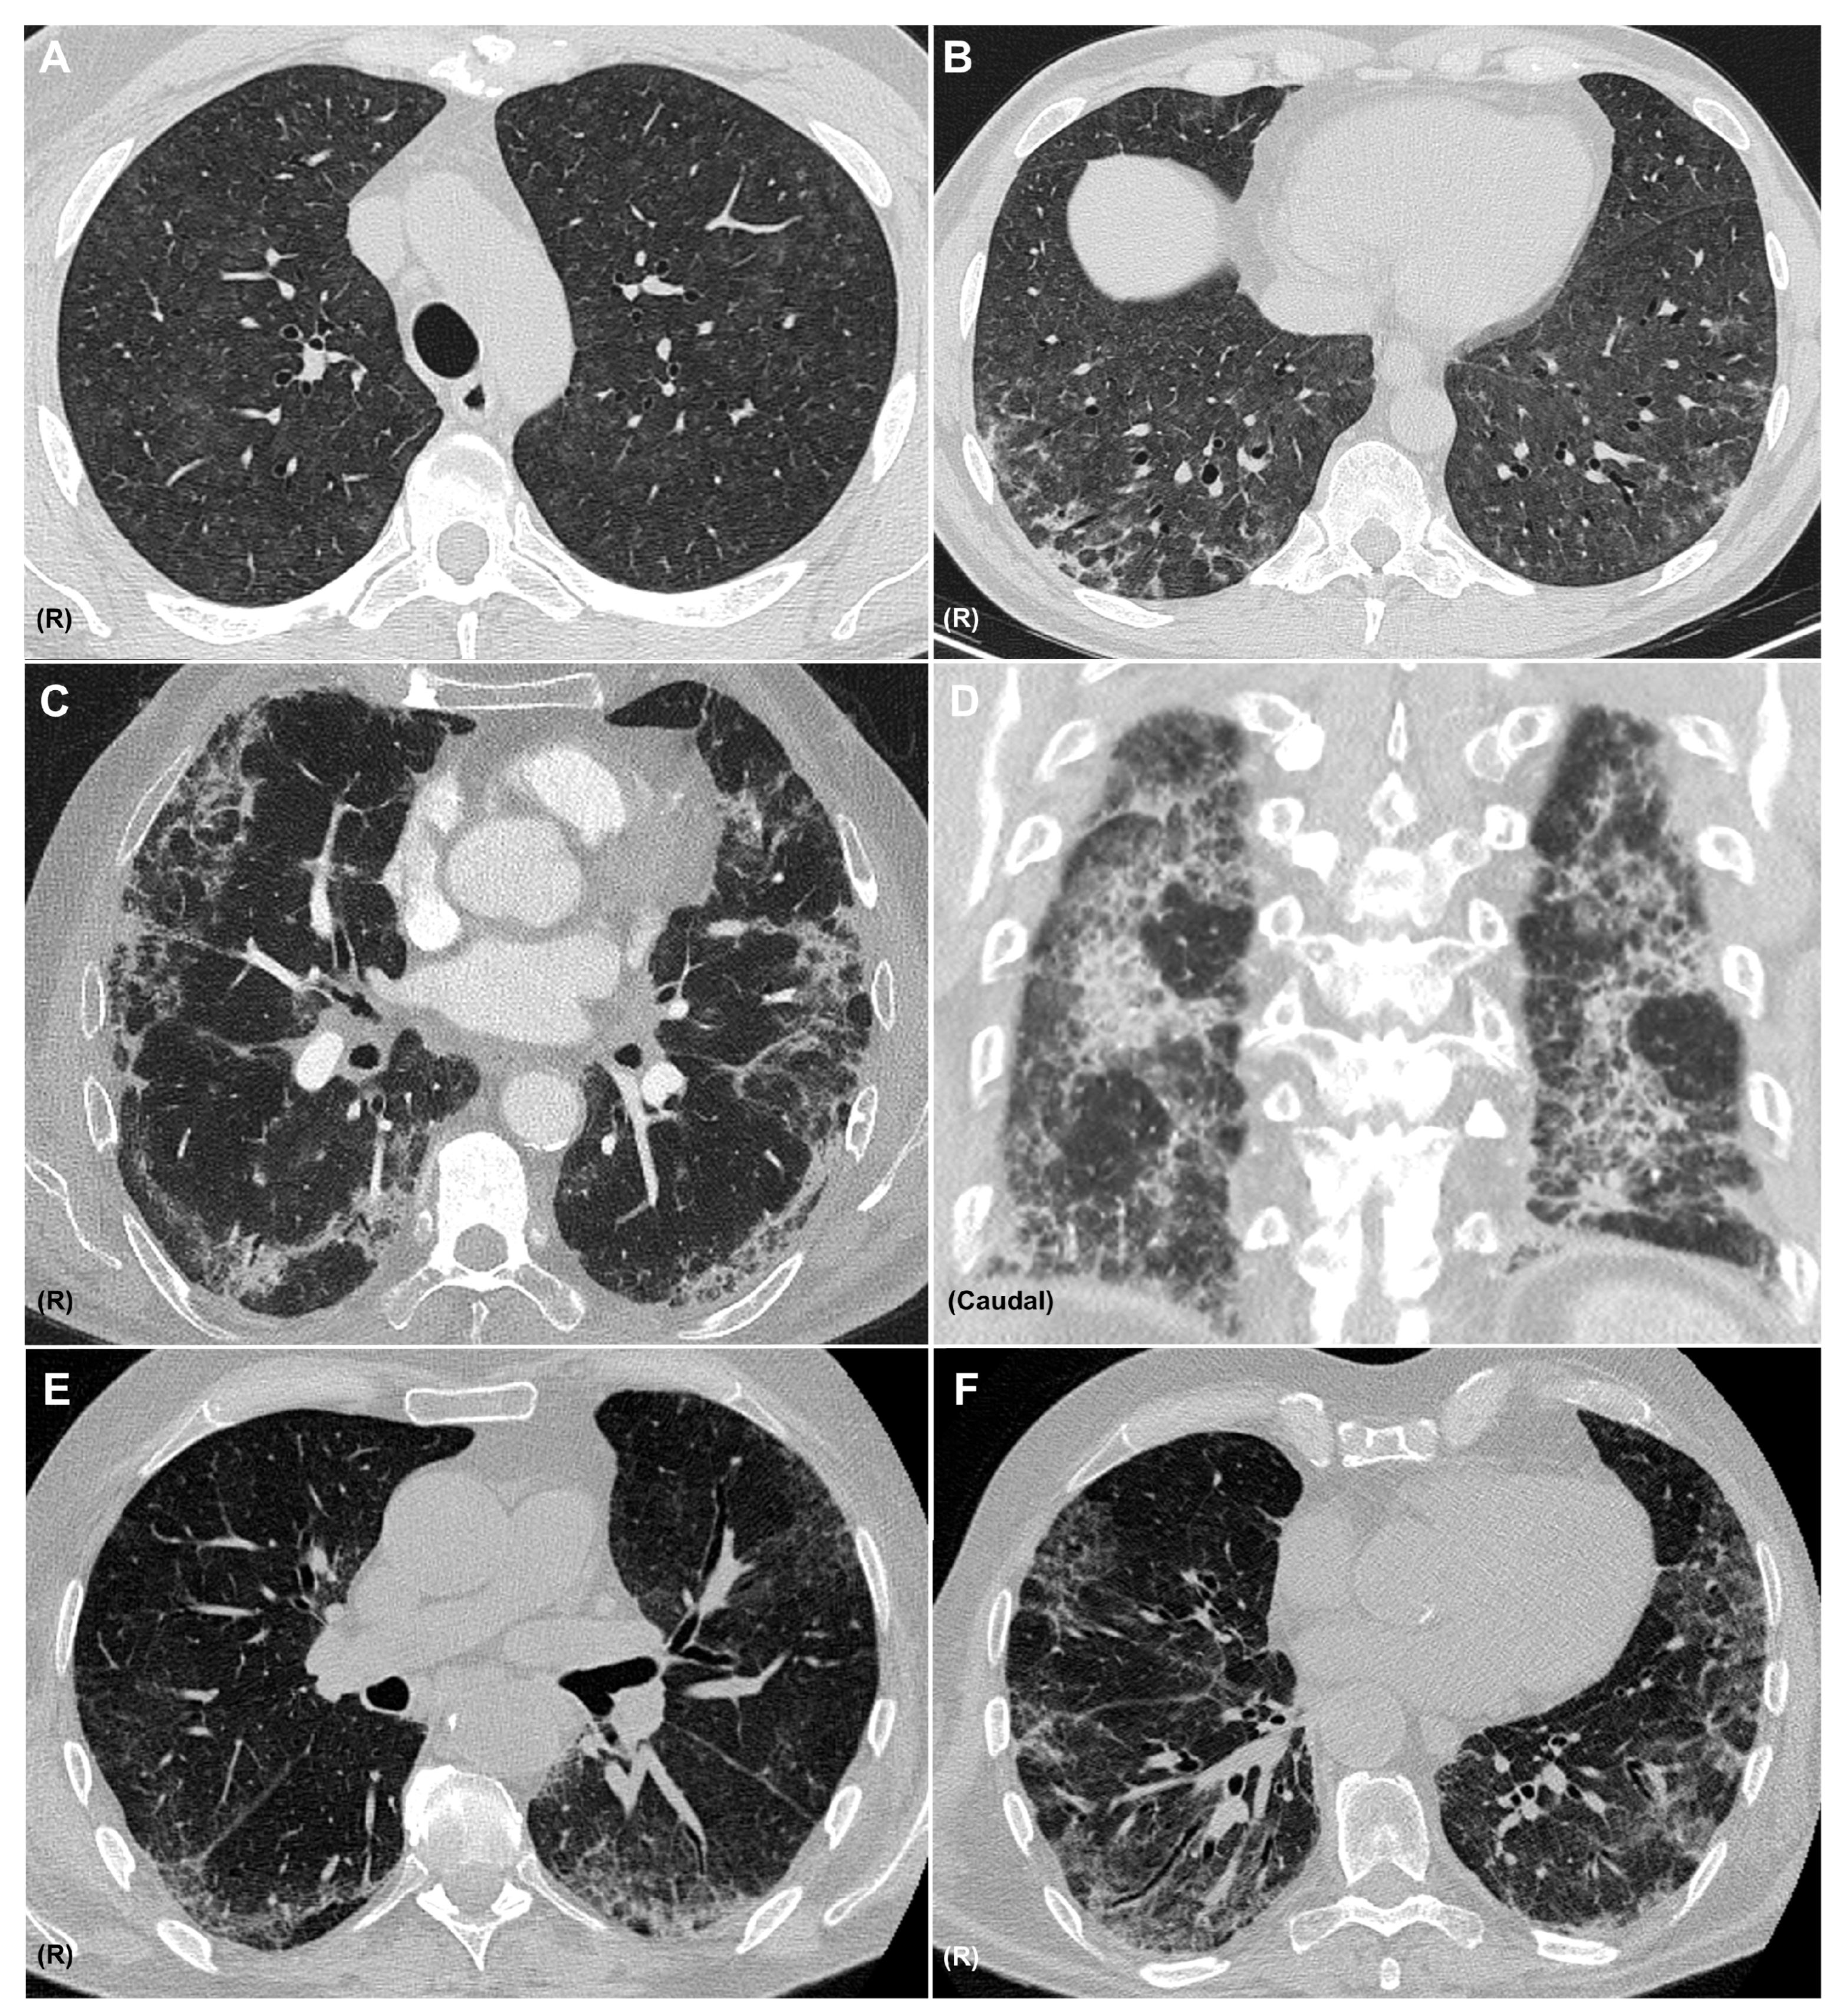

A diagnosis of pneumonitis should be considered when new pulmonary opacities appear on CT in temporal association with immunotherapy, after alternative etiologies—such as infection or tumor progression—have been excluded. It is important to recognize that a single agent may produce diverse radiologic patterns and that multiple patterns may coexist in the same patient (Figure 3). The most frequent CIP radiologic patterns are described in Table 2, in association with the sarcoid-like reaction.

Figure 3.

CT Patterns of Immune-Related Pneumonitis. Axial CT images showing a combined pattern, with non-fibrotic hypersensitivity pneumonitis characterized by diffuse centrilobular ground-glass nodules (A) and perilobular consolidative foci consistent with organizing pneumonia (B), in a patient with melanoma treated with nivolumab and ipilimumab. Axial (C) and coronal (D) CT images showing a combined nonspecific interstitial pneumonia (NSIP) pattern with ground-glass opacities, reticulation, and areas of subpleural sparing, along with consolidations consistent with organizing pneumonia, in a patient with pulmonary adenocarcinoma receiving pembrolizumab. Axial CT images (E,F) showing an NSIP pattern with ground-glass opacities, areas of subpleural sparing, reticulation, and traction bronchiectasis in a patient with clear cell renal carcinoma treated with nivolumab. R: right side. All CT images are fully anonymized and contain no identifiable patient information; therefore, no individual consent was necessary.

The most frequently reported CT patterns in CIP include organizing pneumonia (32%) and hypersensitivity pneumonitis (16%) [24]. However, in other studies—such as the series by Naidoo et al.—ground-glass opacities (GGO) have been identified as the most common radiological finding [34].

CT imaging also plays a role in assessing the severity of pneumonitis. Severe cases are commonly associated with diffuse alveolar damage or organizing pneumonia [52]. In contrast, milder presentations typically show features consistent with hypersensitivity pneumonitis or nonspecific interstitial pneumonia (NSIP) [48].